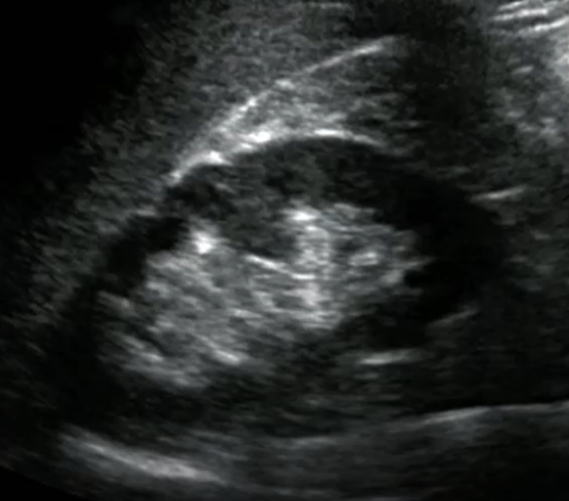

What normal variant of the kidney may mimic a renal mass or duplicated urinary system?

Hypertrophied Column of Bertin

Prominent folds of renal cortical tissue that protrude down into the medulla towards the renal sinus

Clearly separated from the renal sinus

Continguous with renal cortex

Echogenicity is the same as the cortex/renal parenchyma

Not over 3 cm in size as a rule